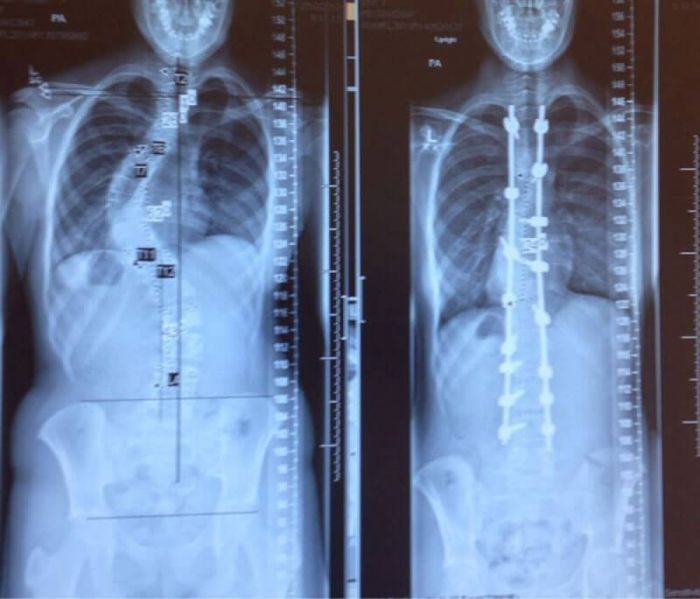

Позвоночник одного и того же человека до и после лечения сколиоза